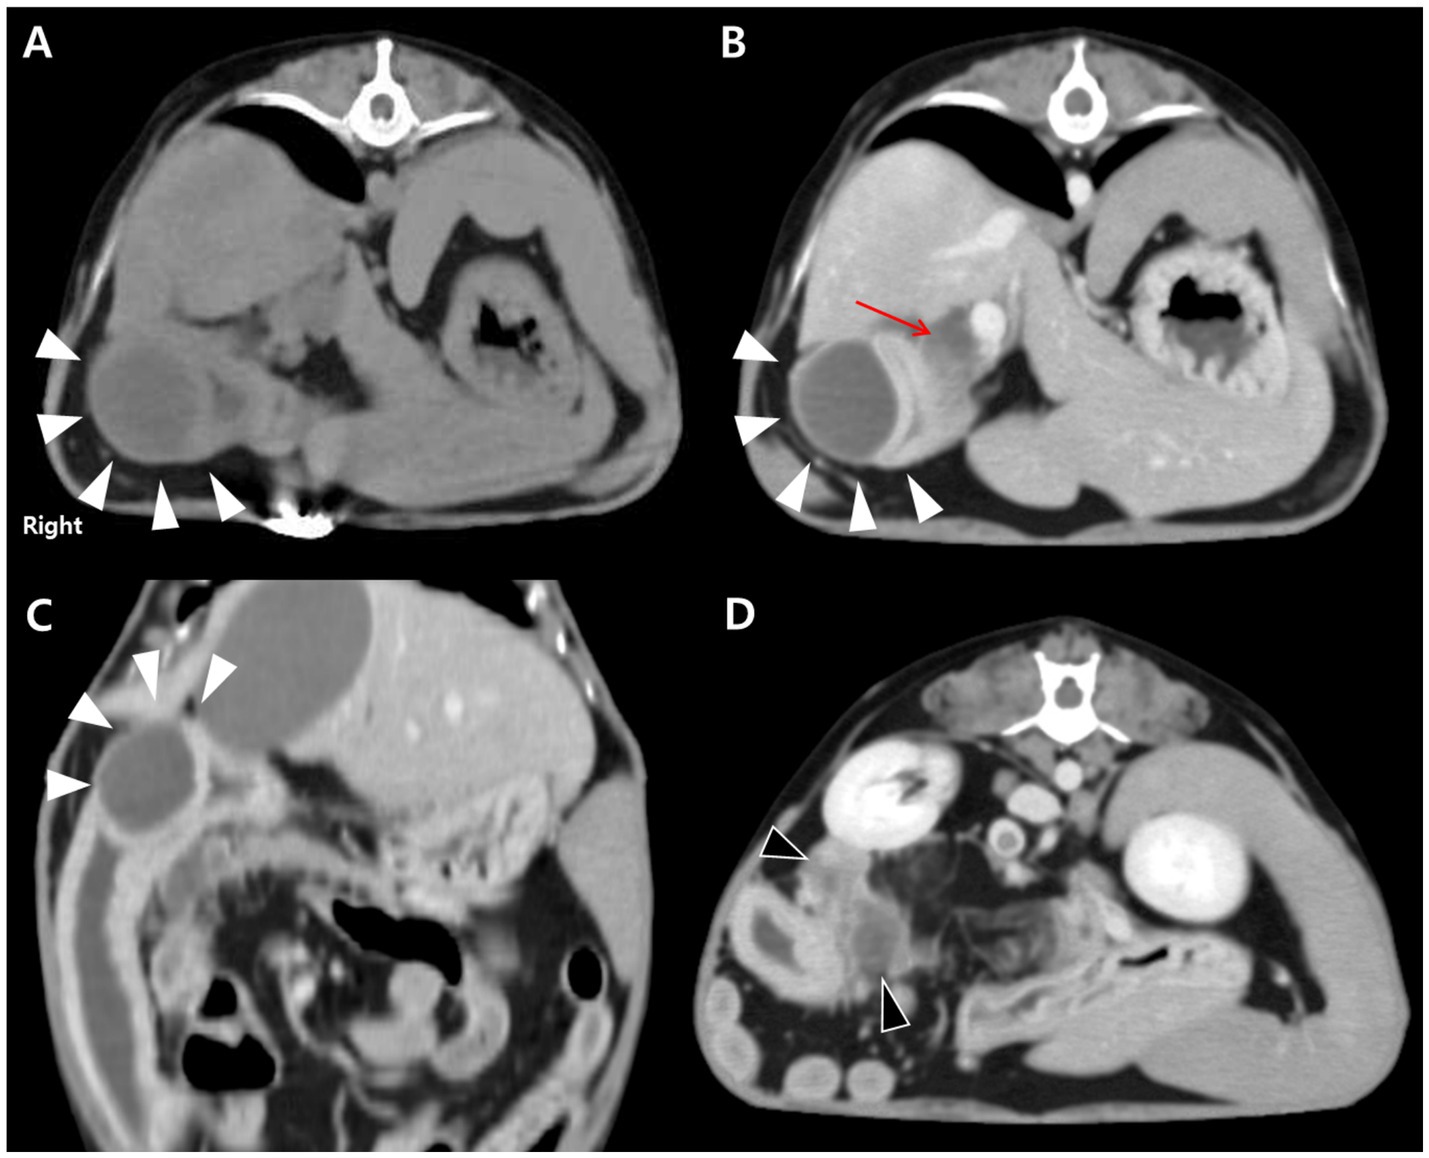

For further evaluation, contrast-enhanced CT was performed after stabilization under general anesthesia with endotracheal intubation and standard monitoring (ECG, SpO₂, capnography, and non-invasive blood pressure). A well-defined, encapsulated, fluid-attenuating mural lesion was identified in the proximal descending duodenum, near the major duodenal papilla and the opening of the CBD (Figures 2A–C). The lesion exhibited peripheral contrast enhancement and central hypoattenuation. CT also revealed CBD dilation (6.15 mm) and pancreatic changes characterized by diffuse hypoattenuation, which was considered compatible with edema (Figures 2B,D). Pancreatic lipase immunoreactivity (PLI) was not assessed in this case. The suspicion of secondary pancreatic involvement was based on the combination of elevated serum amylase and lipase activities, which have limited sensitivity for pancreatitis, together with contrast-enhanced CT findings of diffuse pancreatic hypoattenuation compatible with edema. Taken together, these findings supported the diagnosis of an inflammatory duodenal mural mass, considered the likely cause of secondary extrahepatic biliary obstruction and reactive pancreatic involvement.

Figure 2. CT findings of an intramural duodenal abscess and associated biliary and pancreatic changes in a dog. (A) Transverse pre-contrast CT image showing a well-demarcated, fluid-attenuating, round mural lesion in the proximal descending duodenum (white arrowheads). (B) Transverse post-contrast image demonstrating peripheral rim enhancement of the lesion (white arrowheads) with central hypoattenuation. Marked dilation of the biliary tree, including the cystic, hepatic, and common bile ducts, is evident (red arrow). (C) Dorsal post-contrast image further delineating the lesion (white arrowheads) adjacent to the major duodenal papilla. (D) Transverse post-contrast image showing diffuse hypoattenuating changes in the pancreas (black arrowheads), consistent with reactive pancreatic involvement.